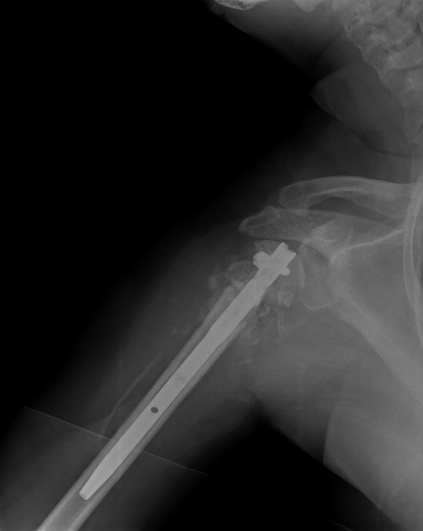

Пошли на операцию, будучи готовыми как к фиксации, так и к протезированию.

Головка с краев была неполная, но для двух винтов места хватило. Сделали

что-то вроде гемиартропластики собственной головкой. Бугорки фиксировали,

как при эндопротезировании.

Снимки вот.